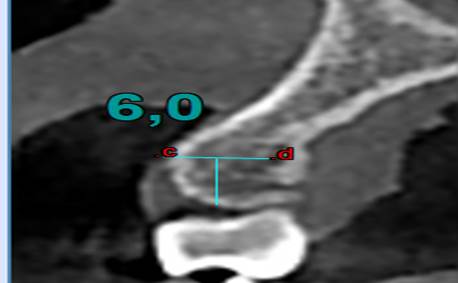

§ Por cada corte se tomaba en cuenta 0.5 mm desde la cresta alveolar hacia la zona de la línea mucogingival. (imagen 1)

§ Con una profundidad de 0.6 mm a través de la cortical hacia la tabla ósea que es el valor mínimo de un microtornillo ortodóntico en sentido horizontal (imagen 2) interradicular. Las Zonas a medir fueron:

Finalmente se mide las Unidades Hounsfield (UH) a 6 mm intraóseo e interradicular. (Imagen 1,2,3,4).